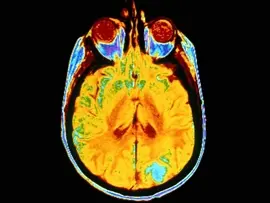

또한 뇌 스캔검사결과 levamisole 수치가 높을수록 사고 손상과 연관이 있었으며 전두엽 피질의 두께가 얇았다.

이는 levamisole 이 뇌에 독성효과를 끼친다는 것을 보여주는 것이라고 연구진은 설명했다.